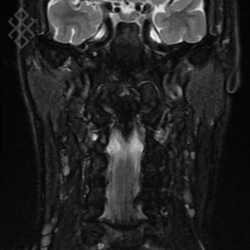

IRM des Parotides

La durée moyenne de l'examen est de 35 min. Dans le cas d'une injection, le manipulateur en radiologie vous administrera le produit de contraste. Vous entendrez un bruit caractéristique à l'IRM faisant penser à un marteau piqueur. Pendant certaines séquences, pour limiter les mouvements de déglutition, il ne faudra pas avaler la salive.